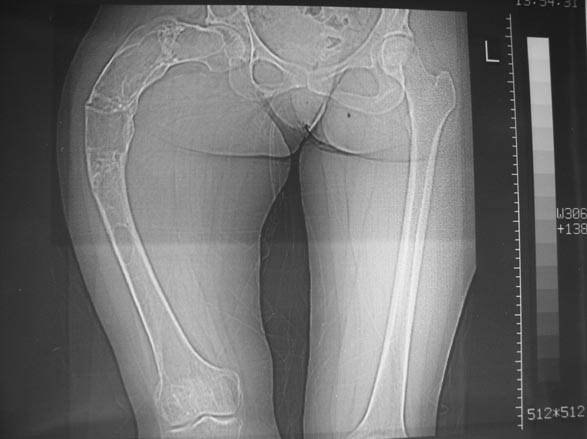

Деформация бедра

Уважаемые коллеги! С Новым годом и самых светлых пожеланий!В ноябре этого года я обращался с просьбой о помощи в выборе тактики лечения больной с деформацией бедра на почве фиброзной дисплазии. Были получены интересные и очень полезные советы по операции.

Хотелось бы показать, что получилось в результате.Операция выполнялась с помощью А.Н.Челнокова. Очень понравилась технология выполнения блокируемого остеосинтеза с использованием спицевого дистрактора, модифицированный гвоздь с латерализованным проксимальным отделом и возможностью многовинтовой фиксации проксимального и дистального участков бедра.

Прекрасная работа, поздравляю Александра и Леонида с удачной реконструкцией: длины и контура бедра.